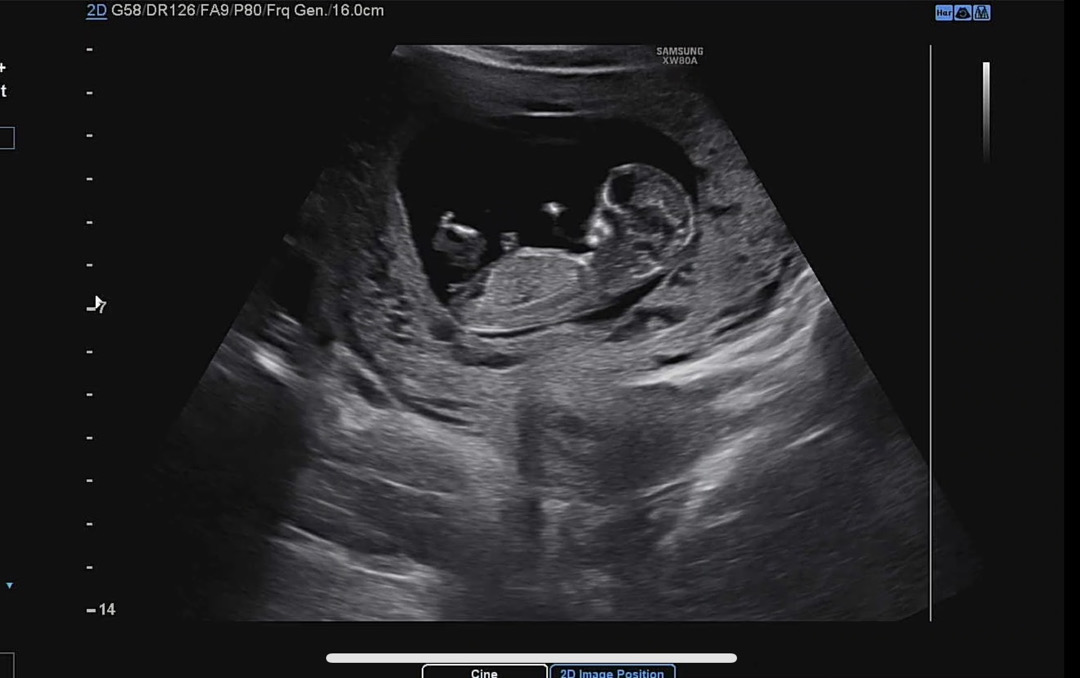

12주 3일차 각도법 부탁드려요!

각도법 아무리봐도 전 감이 안오네요ㅠㅠ 투표부탁드려요..!